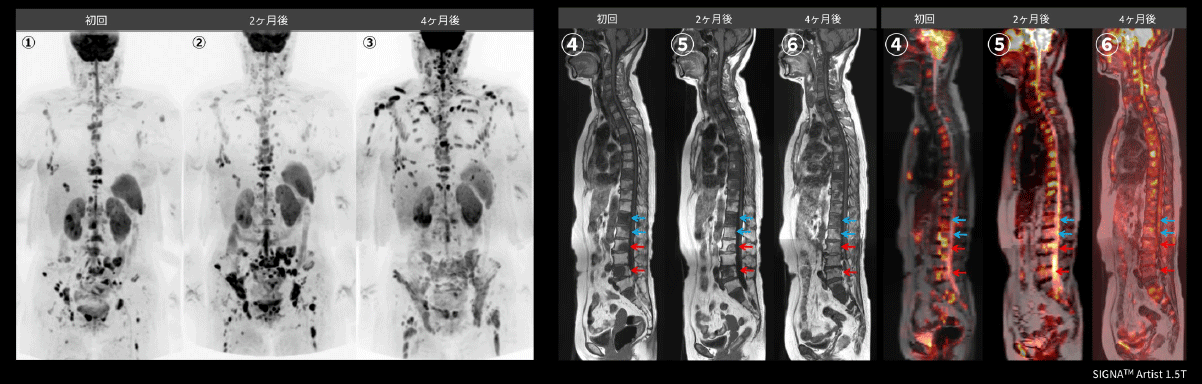

Case2 耳鼻咽喉科:原発不明癌の骨転移に対する治療効果判定

60代、女性。原発不明癌の左頸部リンパ節転移術後、多発骨転移が出現し、第3腰椎(➞)と第5腰椎(➞)に放射線治療後、薬物療法後の骨転移病変の現状評価目的にてWBDWIを施行した。2ヶ月毎に治療効果判定を行っており、WBDWI(①②③)を比較すると腰椎、骨盤骨の信号強度は低下しているが、上腕骨や肋骨の骨転移は新たに出現している。T1WI(④⑤⑥)でL3、L5(➞)の椎体の低信号は消失しており、Fusion画像(④⑤⑥)においても信号強度の低下を認めるため、治療効果があることが示唆される。L1、L2(➞)も同様の所見である(図14)。依頼医からは、PET/CTと比較してWBDWIは早期の治療効果判定に有用であると評価が得られた。

Architect_Okazakishimin02_17.png図14 原発不明癌の骨転移の治療効果判定